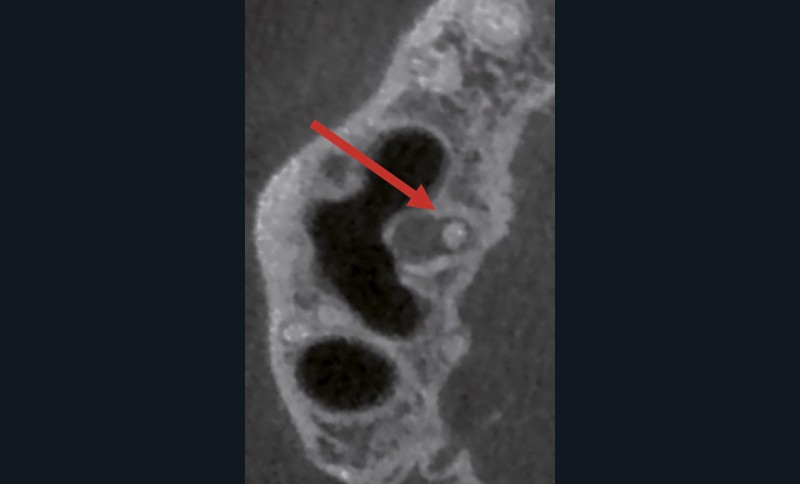

Endal, en 2011, montrait également, en utilisant le micro CT Scanner, l’insuffisance de nettoyage des isthmes inter-canalaires à nos techniques conventionnelles [19]. L’utilisation du laser Er:YAG devenait alors incontournable dans le nettoyage de ces isthmes et des zones non instrumentées (fig. 2 et 3).

Cette pénétration s’étend de la chambre pulpaire au réseau canalaire, isthmes, deltas apicaux et tubulis dentinaires. Il a été démontré que l’effet de cavitation pourrait permettre la destruction des bactéries à des profondeurs de 300 à 400 µm au sein des surfaces irradiées [20].

Si l’étude de Peters [18] nous montre que l’instrumentation laisse 35 % du volume canalaire non instrumenté, Ricucci et Siqueira montrent que la préparation physico-chimique n’élimine que partiellement les tissus nécrotiques à l’entrée des canaux latéraux, des isthmes et des ramifications apicales, en laissant des tissus enflammés et infectés, en association avec des lésions apicales [29] (fig. 4 et 5).

Fig. 4 – Coupe d’une racine mésiale de molaire mandibulaire avec deux canaux traités. Coupe à 3 mm de l’apex, coloration Brown et Brenn, technique modifiée par Taylor. Ces images montrent un isthme étroit avec une infection bactérienne, ce qui prouve l’importance de désinfecter et d’inclure l’isthme dans les traitements conventionnels et dans les rétropréparations apicales en chirurgie endodontique.